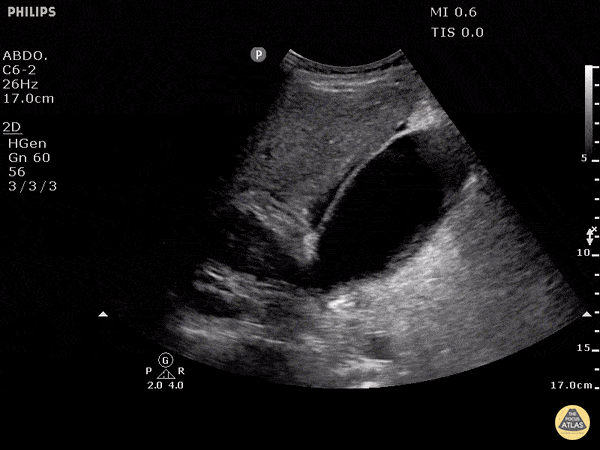

Biliary - Pericholecystic Fluid

Free fluid can be appreciated around this gallbladder. This is called pericholecystic fluid. However there are no stones, nor gallbladder wall thickening, and the sonographic Murphy's is negative. This free fluid is unlikely to be caused by cholecystitis. In this case, the free fluid came from a different source. Justin Bowra MBBS, FACEM, CCPU Emergency Physician, RNSH et al.